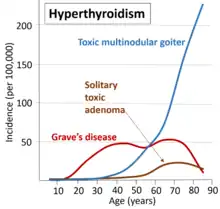

| Most common causes of hyperthyroidism by age.[1] | |